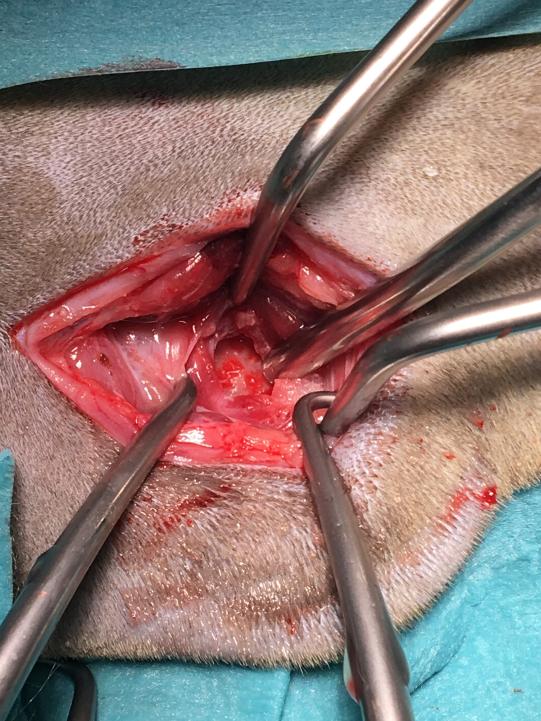

Ein externer Chirurge wird zur heiklen Operation beigezogen. Vorsichtig wird die Knochenwand des Mittelohres eröffnet und versucht, die Wucherung zu entfernen. Es stellt sich aber heraus, dass der Polyp auch im Gehörgang festgewachsen ist, weshalb auch ein Teil des Gehörganges entfernt werden muss.